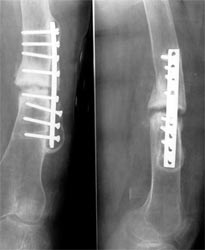

病例三、患者42岁,股骨中1/3骨折骨不连2年,钢板手术失败,明显畸形。

采用上述方法成功治愈。